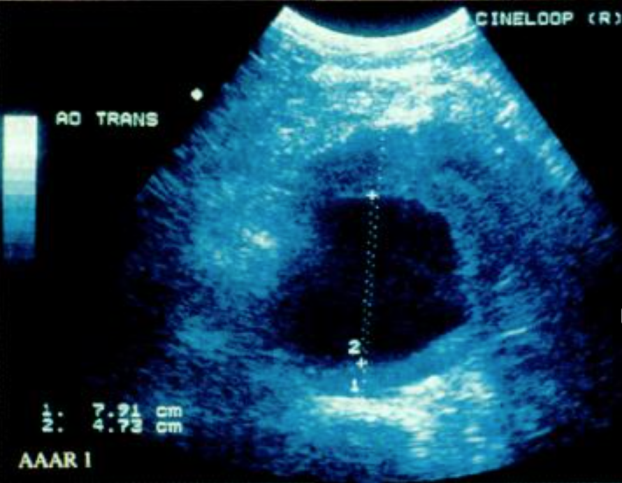

Скрининг и раннее выявление. Скрининг АБА является ключевым направлением профилактики осложнений, поскольку позволяет выявлять заболевание на доклинической стадии. Ключевым методом скрининга является ультразвуковое исследование брюшного отдела аорты, обладающее высокой чувствительностью и специфичностью, достигающими 94–100 % и 98–100 % соответственно [3, 6]. Типичная ультразвуковая картина при аневризме брюшной аорты представлена на рисунке 4.

Рис. 4. Аневризма инфраренального отдела аорты. Поперечное ультразвуковое сканирование в В-режиме [7, с. 27]